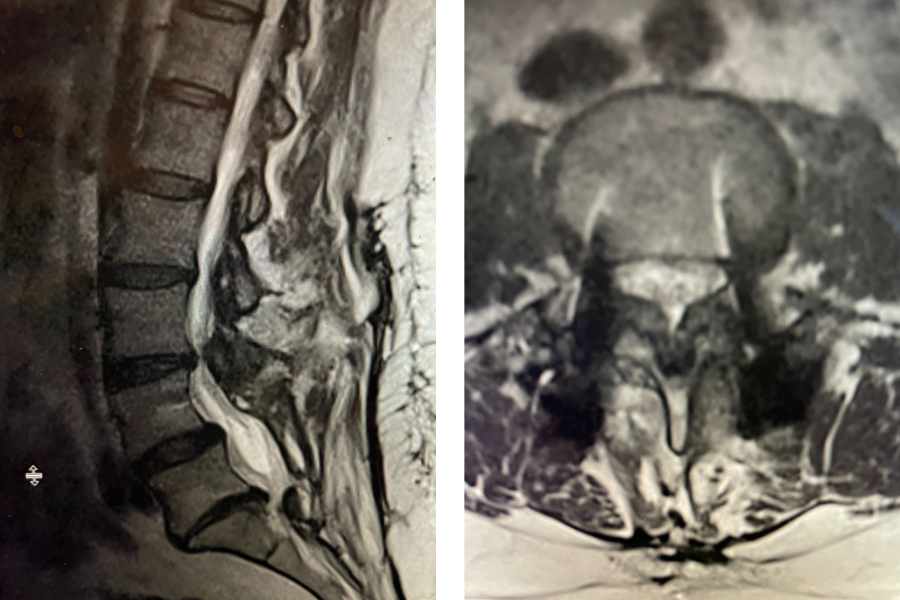

Figure 1. Sagittal and axial T2-weighted MRI of the spine demonstrating severe next segment stenosis above the prior fusion worse at L3-4 mainly due to severe ligamentous hypertrophy

This next patient was a 54-year-old female who had a long history of low back pain with radiation to both legs. She had a prior L4-S1 instrumented fusion and a L3-S1 laminectomy two years prior. In the past six months she has developed worsening low back pain and bilateral leg radiation. She had tried medications, epidurals, and PT but with no improvement. Imaging revealed severe stenosis above her prior fusion at L3-4 secondary to thickened ligament and facet hypertrophy or enlargement. This was also evident slightly less so at L2-3 (Fig 1). This ligament is in particular commonly involved in causing lumbar stenosis. This is a ligament that looks yellow in the operating room for which its purpose normally is to act like a rubber band to limit extremes of flexion and to aid in upright posture. Perhaps this ligament thickens to compensate for the decrease in upright support as we get older. It was decided initially to perform an L2-4 revision laminectomy, explore the prior fusion, and remove the hardware. We would leave the L4 screws in and add screws at L2 and L3, giving her a shorter segment of fusion mass if she was indeed fully fused.